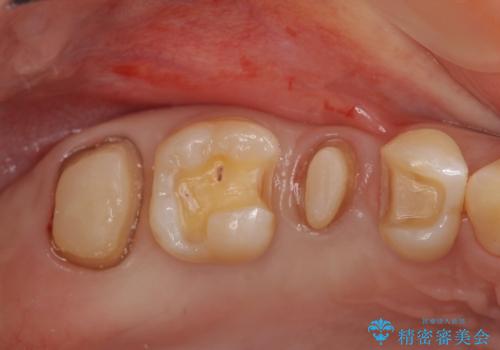

放置した虫歯を外科を行い抜歯を回避

- 放置していた虫歯が欠け、いよいよ怖くなり治療を希望され来院されました。

虫歯は、その進行度によりさまざまな治療法が提案されますが、

エナメル質・象牙質に限局する虫歯 →インレー修復

歯の神経に達する虫歯 →根管治療 クラウン補綴

歯ぐきよりも深い虫歯 →歯周外科による歯周環境の整備

を適宜行うことで良好な結果を得ることができます。

症状に応じて適切な処置を行ったことで、抜歯を回避し良好な結果を得ることができました。